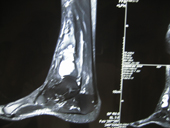

| Giant cell tumour MRI |

MRI2 |

MRI3 |